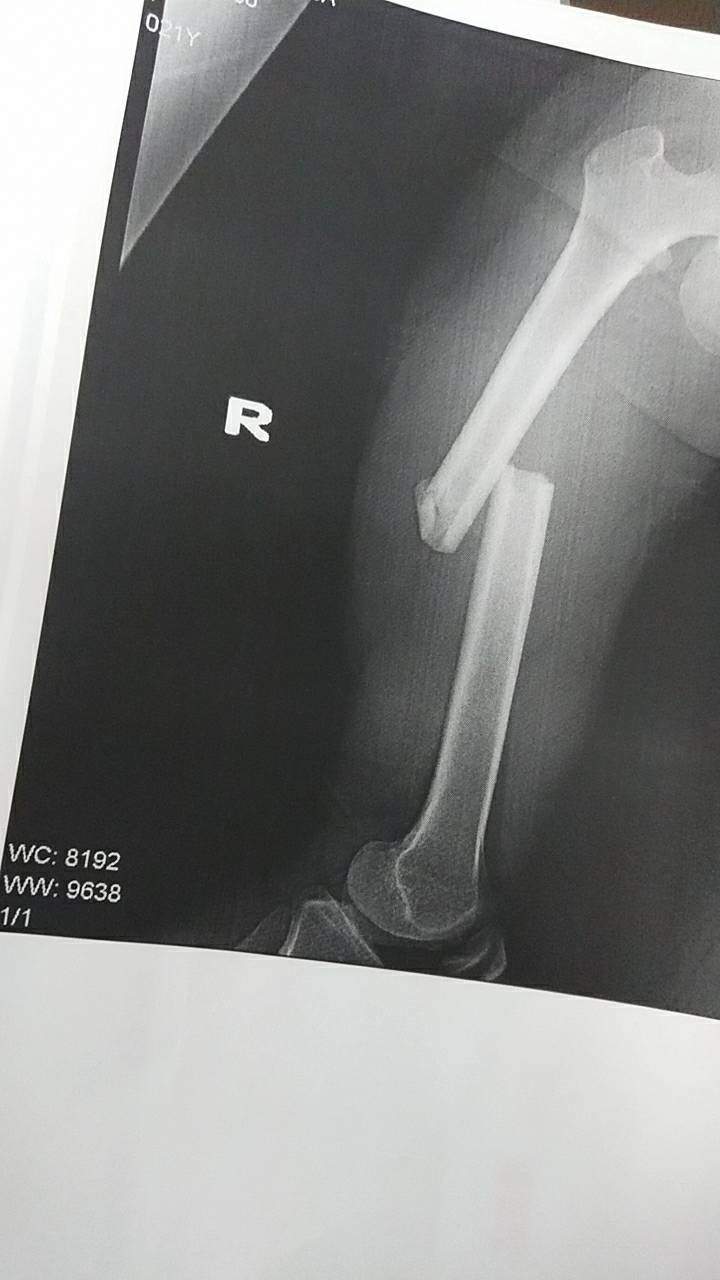

其實不是故意放一些很痛的畫面來刺激大家,我這邊也是冷汗直流手心冒汗,只是骨折大概是什麼程度,樣子大概是怎樣放個示意圖上來看看而已

所以不管是身體檢查的人或是受傷看醫生的人,當拿到X光片的時候,我相信了解自己身體的狀況後,應該就不太會多想,但有推友在這邊找到了創意跟可能性,推主「@mauree__n」就把骨折的X光片,轉印製成褲子穿在身上,大腿骨折該部位就對應褲子圖案的地方,雖然感覺超痛,但衣服真的酷斃了我覺得

太ももの骨折った日に撮ったレントゲンをズボンにした pic.twitter.com/6hWkXowkOm